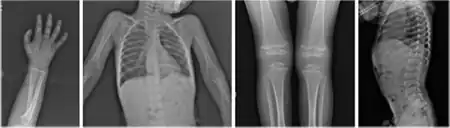

Radiograph of a WRS child presenting with dysplastic bone growth in various regions of the body. | |